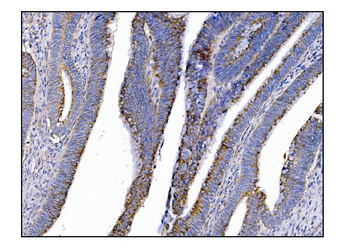

IHC staining of FFPE human colon carcinoma with MerTK antibody (clone TPKR-1). HIER: boil tissue sections in pH9 10mM Tris with 1mM EDTA for 10-20 min and allow to cool before testing.